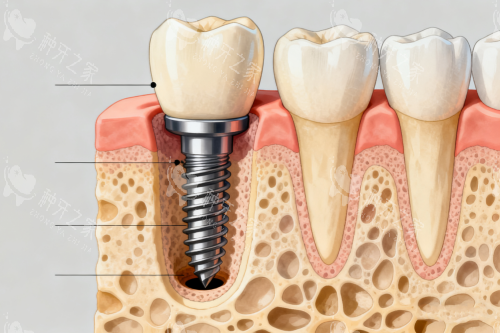

杭州佐伊口腔的种植牙价格体系清晰透明,单颗种植牙的费用根据品牌和技术需求分层报价。

韩国奥齿泰种植牙是这里的入门级主打产品,价格亲民但功能扎实,尤其适合预算有限又追求可靠性的用户。

而诺贝尔种植牙则定位高端,价格翻倍的同时也带来了更丰富的临床病例支持和长期稳定性维持。

佐伊口腔的种植项目由宣灵春院长主导,这位医生在复杂种植病例上积累了大量经验,尤其是All-on-4这种高难度技术,能够用更少种植体实现全口牙齿的功能重建。

医院在数智化种植方面的投入也值得关注,虽然价格比常规种植高出一些,但导板技术能更准控制种植体角度,避免神经血管损伤,对牙槽骨条件欠佳的老年人尤其友好。

奥齿泰作为韩国主流种植体品牌,在即刻负重和技术上已有成熟应用,只是相比欧美品牌在表面处理工艺和长期临床数据上略有差距。